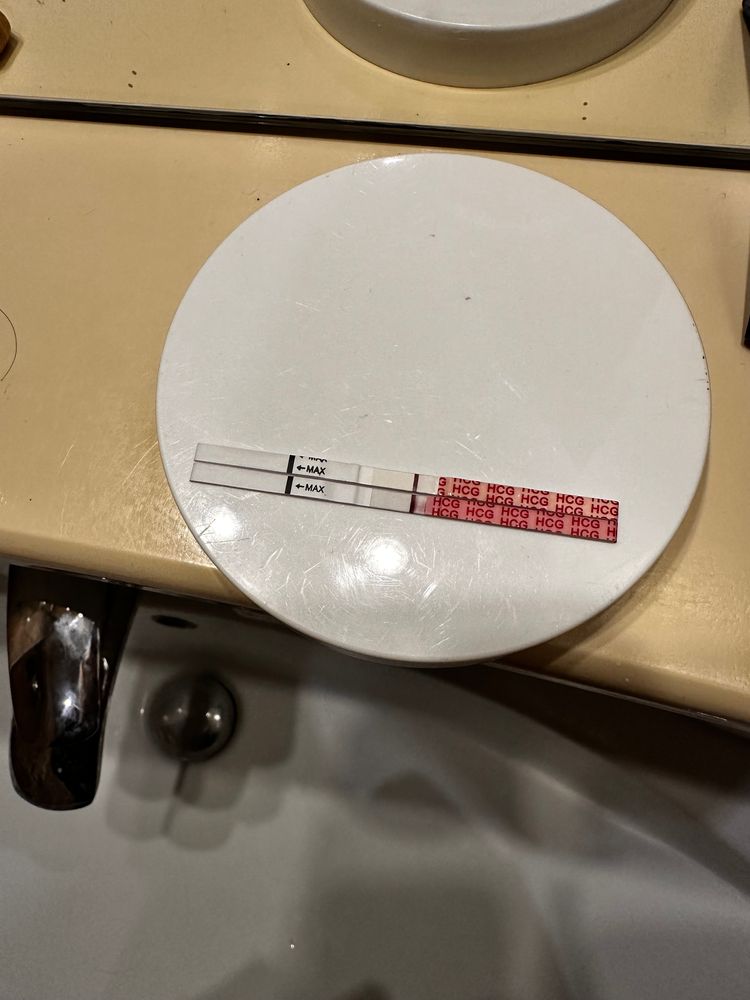

Девачки, почитала всех и короче пошла тесто манить , не могу уснуть теперь 😂😂😂😂 во что получилось напоминаю на 6 дпо

тест на о сегодняшний

Тест с верху старый 2 цикла назад

Тест с верху старый 2 цикла назад

Тест с верху старый 2 цикла назад

Тест с верху старый 2 цикла назад

Алина Горева, что-то есть, но мне кажется тест потек(

лучше переделать